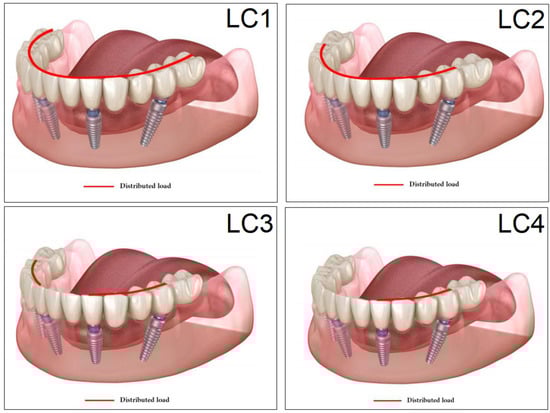

2.6. Loading, Occlusal Cases